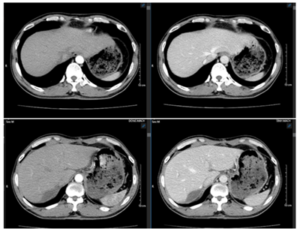

Case lâm sàng: Điều trị bệnh nhân ung thư biểu mô tế bào gan tại Trung tâm Y học hạt nhân và Ung bướu – Bệnh viện Bạch Mai

Case lâm sàng: Điều trị bệnh nhân ung thư biểu mô tế bào gan tại Trung tâm Y học hạt nhân và Ung bướu – Bệnh viện Bạch Mai GS.TS. Mai Trọng Khoa, PGS.TS. Phạm Cẩm Phương, Ths. Lê Quang Hiển, BSNT. Cao Văn Trung, BSNT. Đỗ Đăng Thọ Trung tâm...